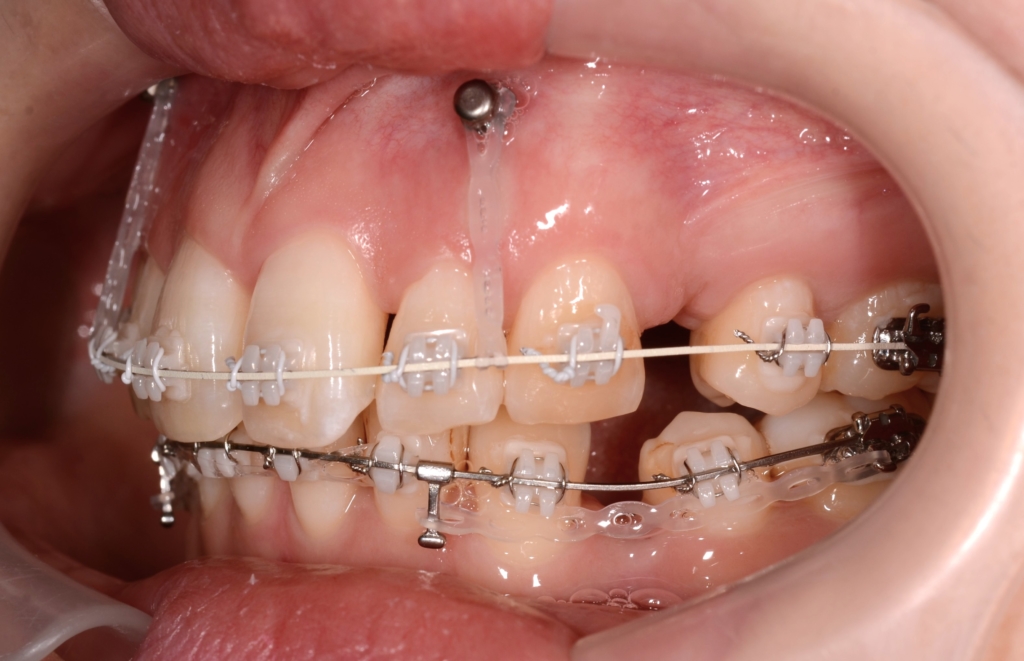

マルチブラケットシステム(ハーフホワイトtype)で矯正を開始。

アンカースクリュー

上の前歯が並んだので、ガミースマイルを改善させるために、前歯部にアンカースクリューを植立して準備を整えます。

そうこうしているうちに、下の歯列も並んで整ったので、

「上の前歯の圧下」と「下の前歯の後方への移動」を同時進行で行うことにしました。

その後、ガミースマイルの改善が済んだので、あらためて「上の前歯も後方への移動」を行いました。

同じ内容の治療をしている方のモノをイメージ写真として挙げています。